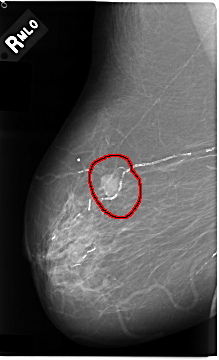

FILE: C_0031_1.RIGHT_MLO.OVERLAY

TOTAL_ABNORMALITIES 1

ABNORMALITY 1

LESION_TYPE MASS SHAPE IRREGULAR MARGINS MICROLOBULATED

ASSESSMENT 5

SUBTLETY 5

PATHOLOGY MALIGNANT

TOTAL_OUTLINES 1

BOUNDARY